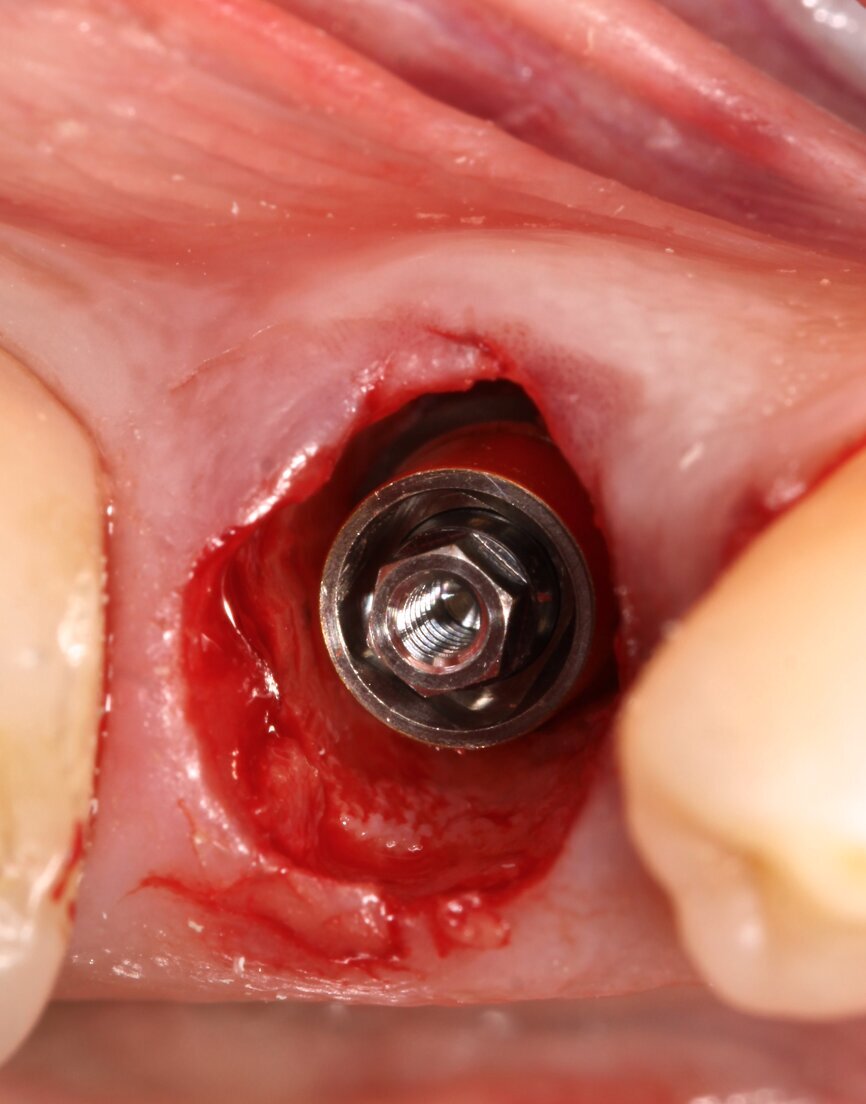

Fig. 3: Implant without intermediate abutment.

A 5 x 15 mm BTI interna plus implant (internal connection) was placed lingually to the SS, taking as reference for 3D positioning the adjacent tooth and implant crowns. The platform of the implant was placed 1 mm below the level of the buccal bone crest and the SS (Fig. 3). A BTI UNIT Transepithelial abutment was used to extend the implant’s platform 0.5 mm subgingivally (Fig. 4).